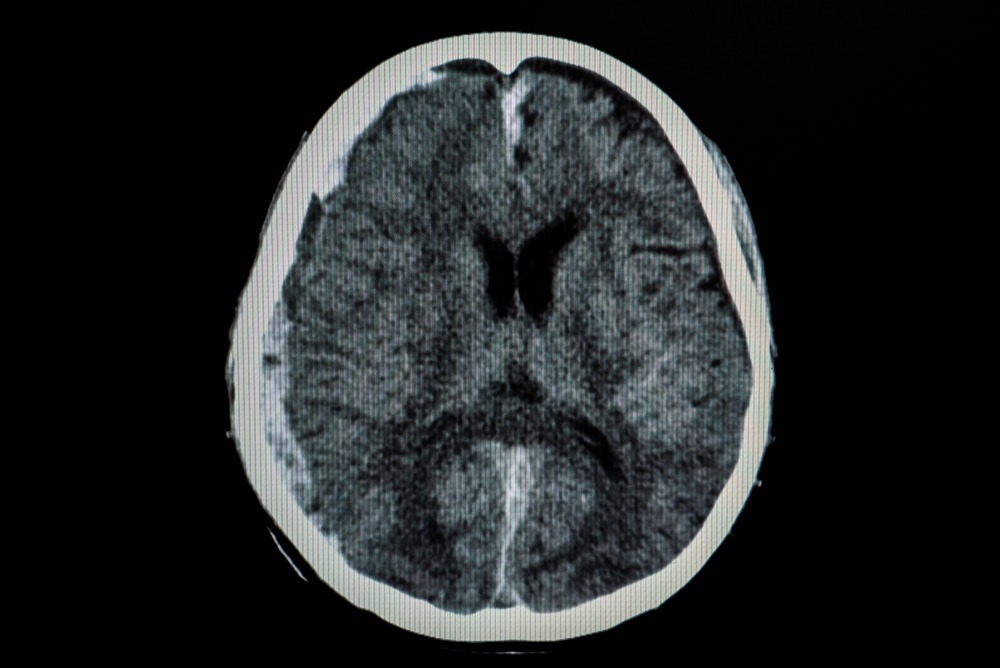

Whether you’ve sustained a traumatic brain injury (TBI) from a car accident, fall, or another type of accident, it goes without saying that it’s a stressful and devastating event for you and your family. TBIs are serious injuries, and the recovery process can be complex. Here’s what to expect:

The first few weeks of a brain injury could mean swelling, bleeding, and changes in brain chemistry. These changes affect brain health. As the brain starts to heal, it will go through these common three stages: